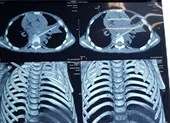

Khai thác bệnh sử trước mổ, ê kíp không phát hiện gì đặc biệt và quyết định mổ nội soi. BS CK2 Vương Minh Chiêu, khoa Ngoại tổng hợp cho hay: “Trong lúc mổ, chúng tôi ghi nhận ổ bụng bệnh nhi rất dơ, có nhiều dịch mủ đục và phát hiện có một dị vật giống que xiên đồ ăn dài 5 cm đâm thủng đoạn cuối ruột non. Đây chính là nguyên nhân gây ra tình trạng viêm phúc mạc”.

Hình ảnh chiếc xiên que đâm thủng ruột bé trai. Ảnh: BVCC